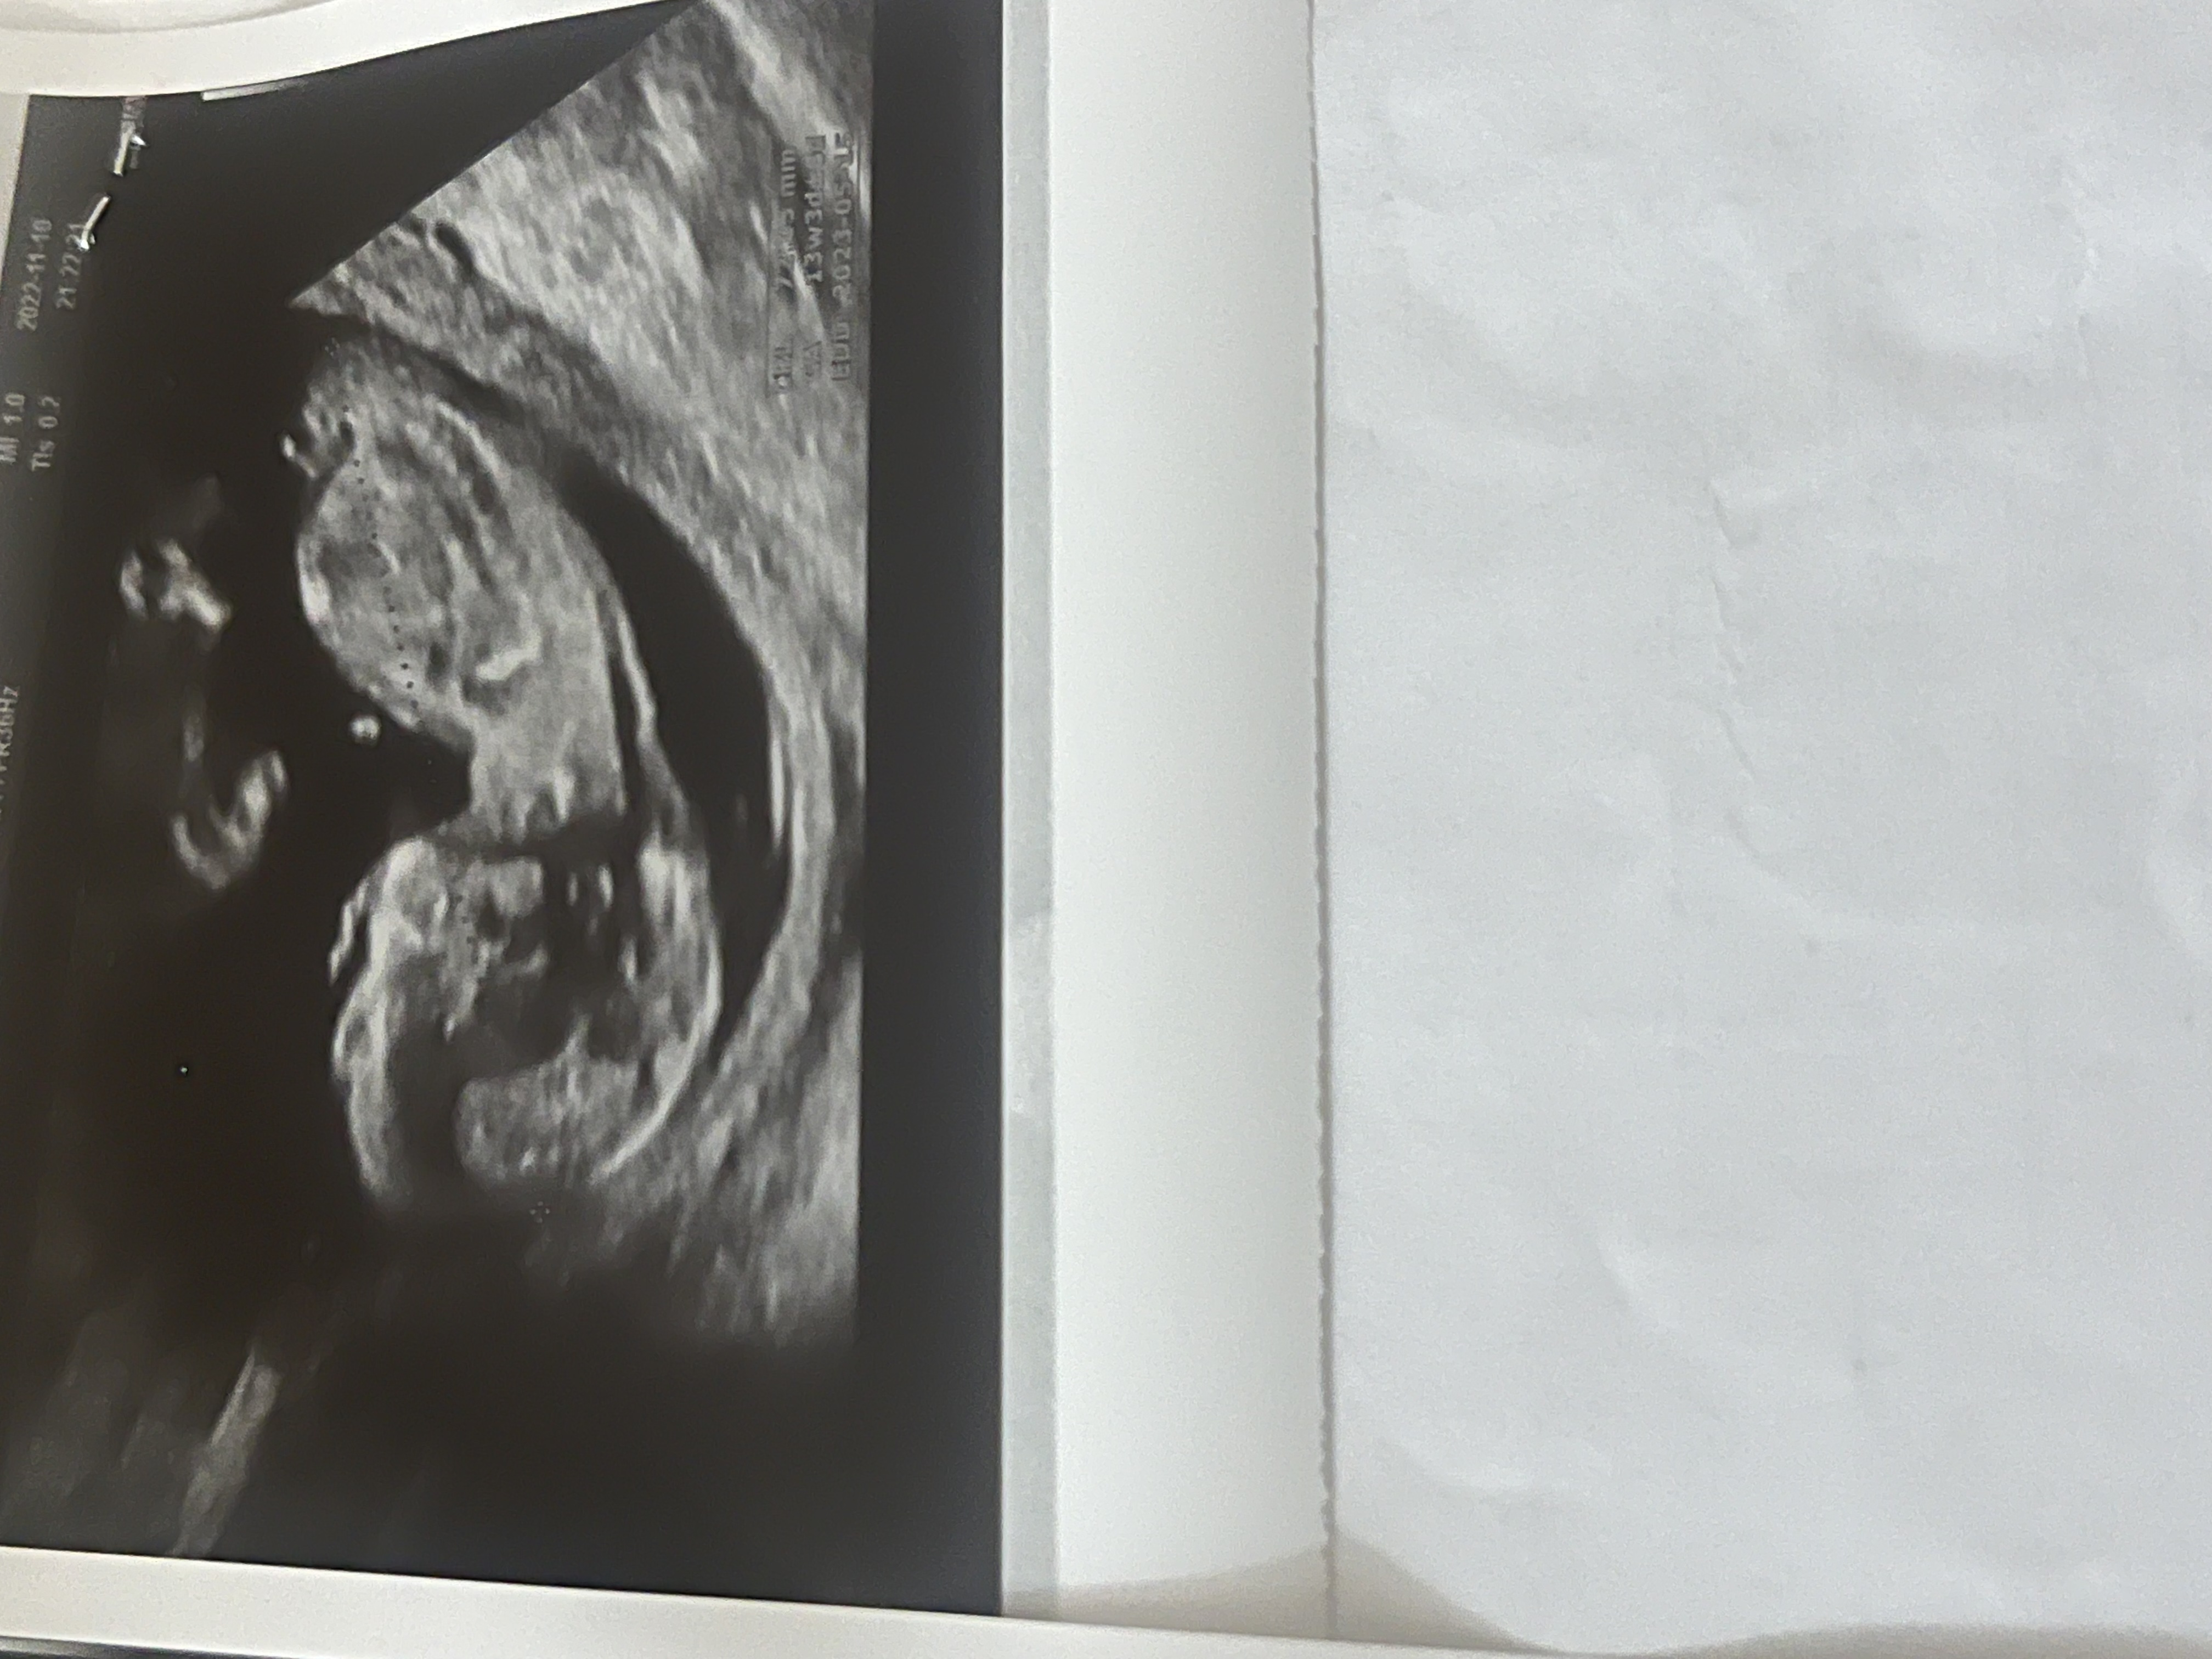

بنظرتون جنسيت چيه ؟؟

الان عكس سونگرافي ميزارم

چن هفته ای؟

نزديك ١٤

ان تي بهم گفت پسره

يني اشتباه گفته؟؟